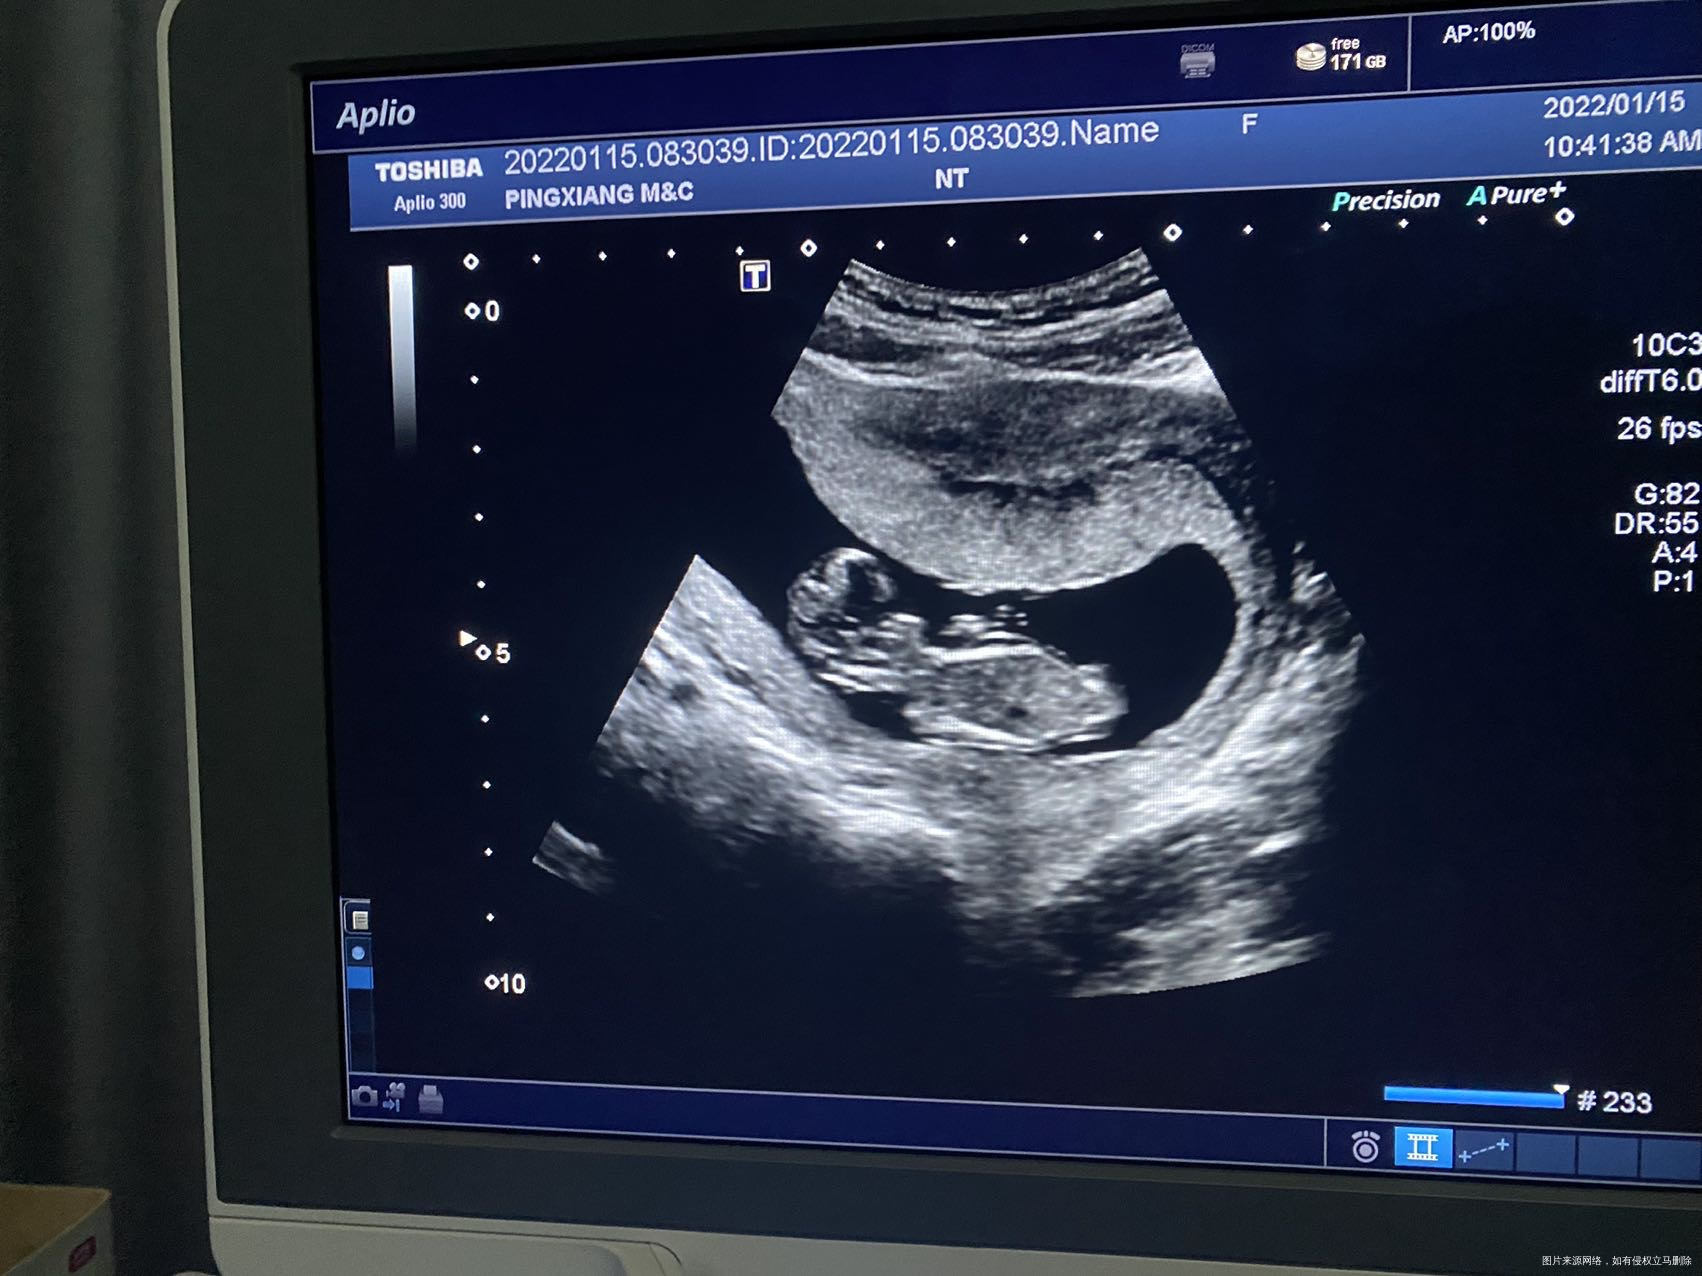

怀孕11周➕1,b超是这样的正常吗

需要看b超单描述的内容

匿名用户 回复 陈丹:今天本来打算做nt 的,医生说还太小,再等一周,就没出b超单

对的,一般12周后再做更好

这个胚胎已经成型了,但是要测量径线还有测心跳这些数据的,如果医生没出报告,那不是很好说,建议等报告出来后才知道呢

胚胎成型,非常好,符合孕周

很好,一般十四周前NT检查,胎儿发育很好